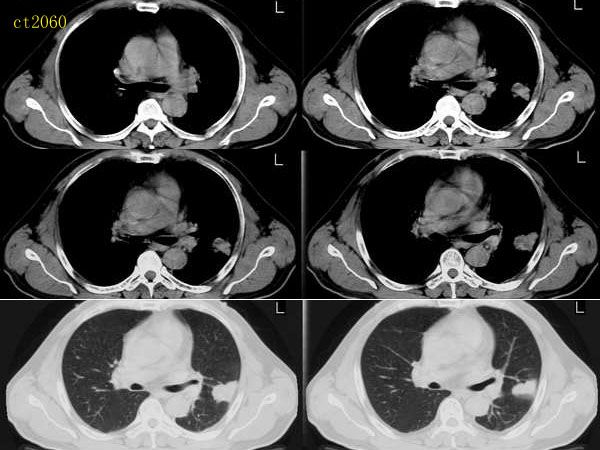

ct2060 liuzhiguang 提供 病理中分化型腺癌

http://www.radida.com/radinet/read.php?tid=8557